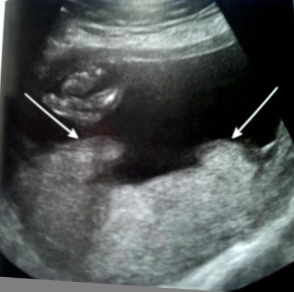

What does this image show?

marginal abruption